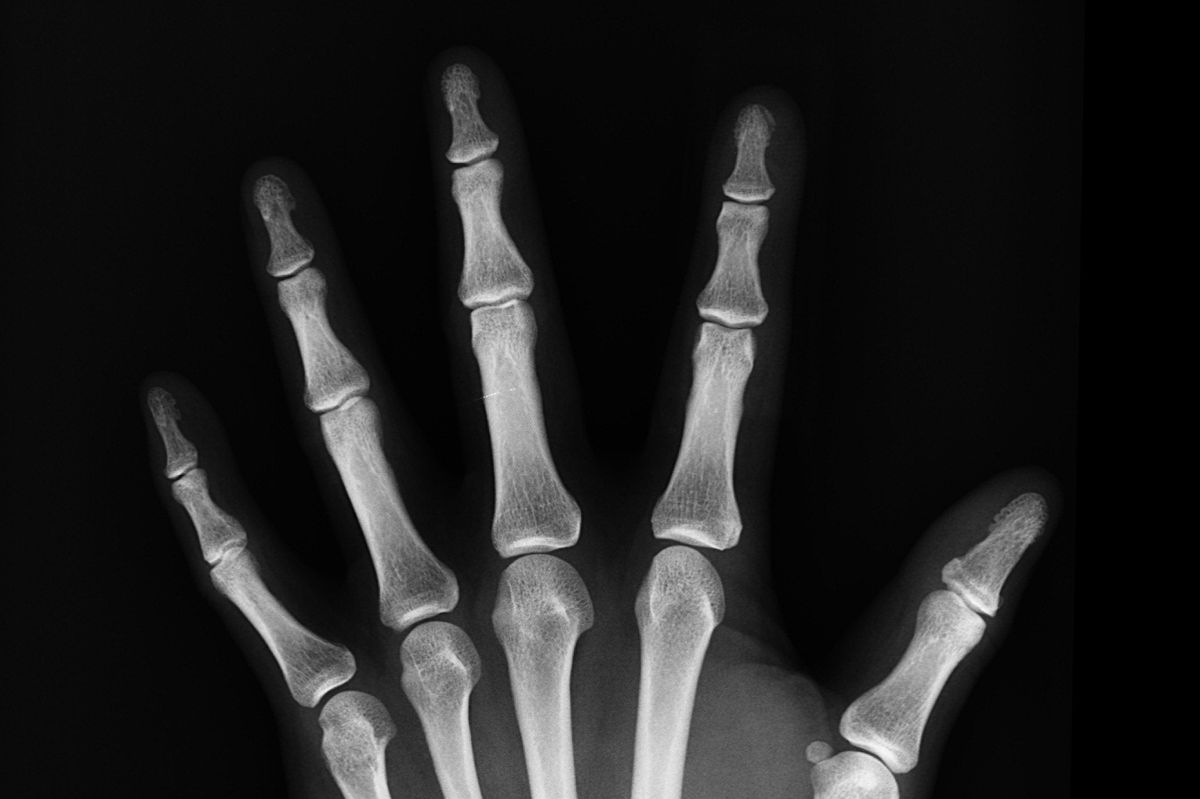

O envelhecimento causa, naturalmente, uma perda de densidade óssea. Além dele, algumas enfermidades e a redução da produção de hormônios sexuais também contribuem para essa perda. Assim, uma dieta pobre em cálcio durante a infância pode ocasionar um acúmulo insuficiente de massa óssea para quando isso acontecer. Evitar esse cenário depende não apenas do consumo de cálcio, mas também da prática regular de atividade física.

A endocrinologista especialista em osteoporose e doenças osteometabólicas, Carolina Aguiar Moreira, explica que as perdas de massa óssea são mais acentuadas nas mulheres após a menopausa e, nos homens, depois dos 50 anos. “Quanto maior o pico de massa óssea, maior a reserva disponível quando essa fase chegar. É importante conscientizar as crianças porque nessa etapa da vida é quando mais aumenta o pico de massa óssea”, conta.